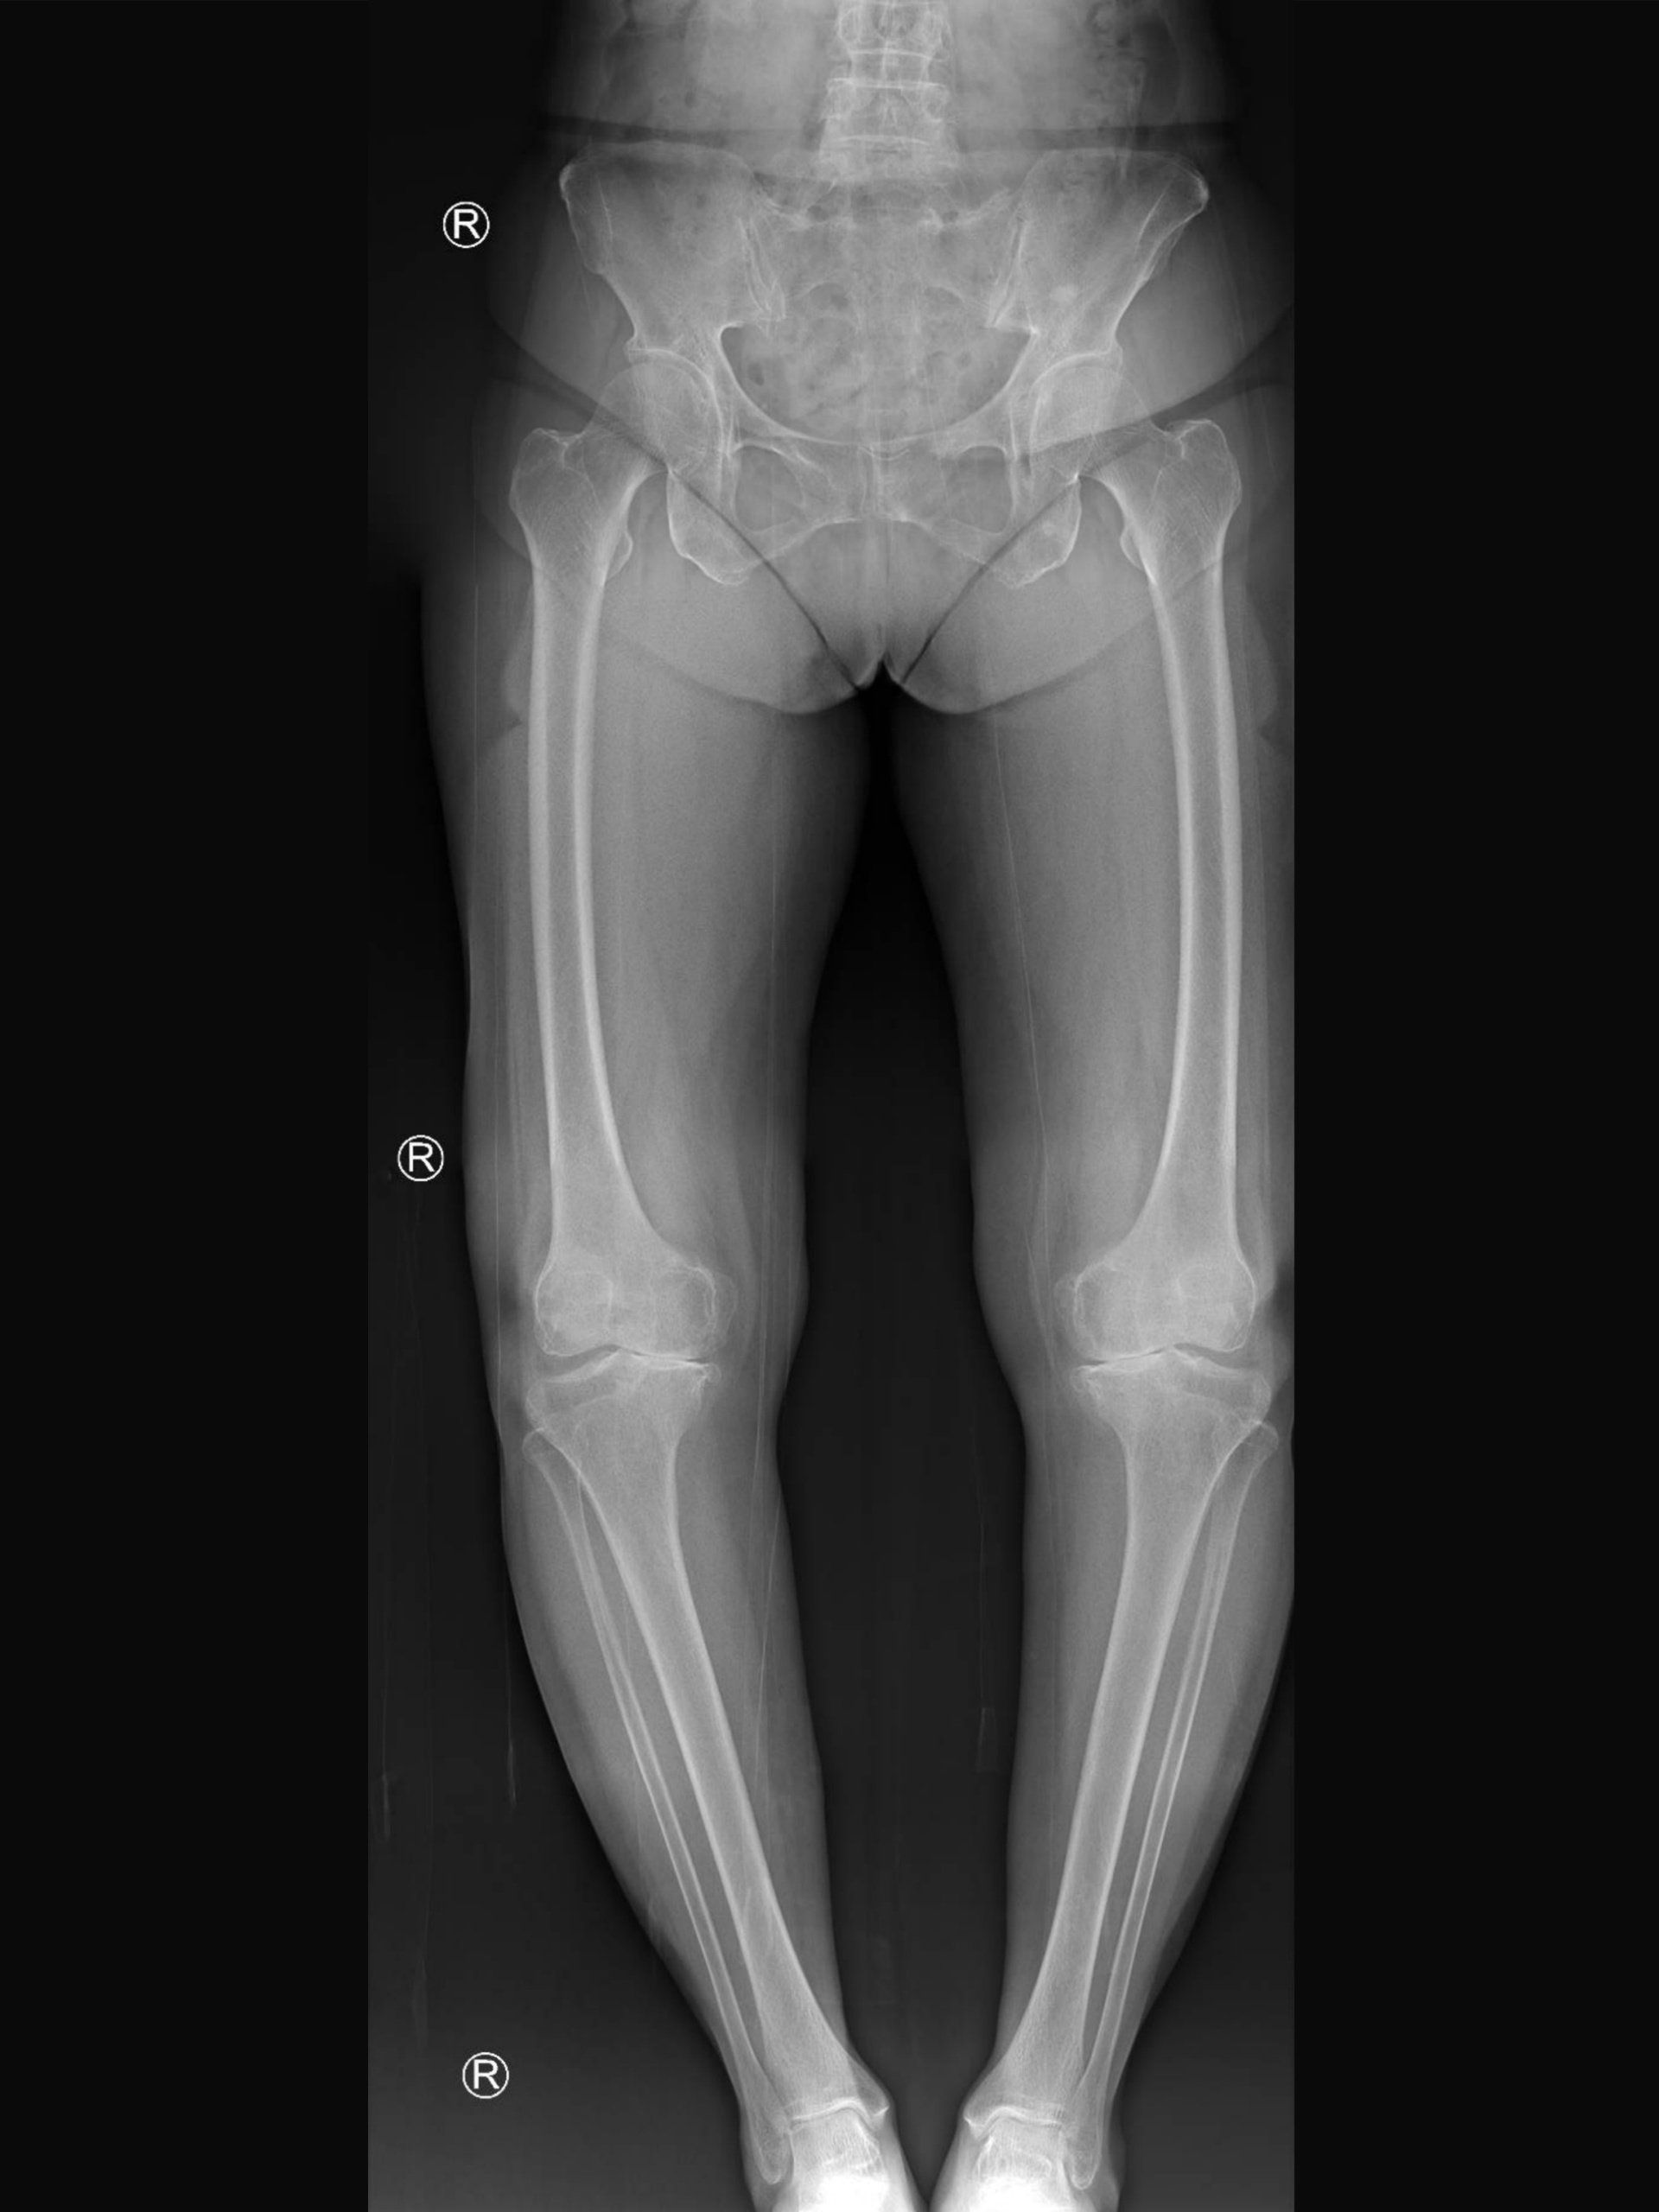

- Long leg alignment views:

- X-rays taken of both lower limbs whilst standing and cover from pelvis to feet

- From the long leg alignment views, the surgeon will be able to calculate the location and degree of deformity, and the amount of correction that is required

- This will then help determine:

- Where to perform the osteotomy (tibia or femur)

- Which type of osteotomy to perform (open or closed wedge)